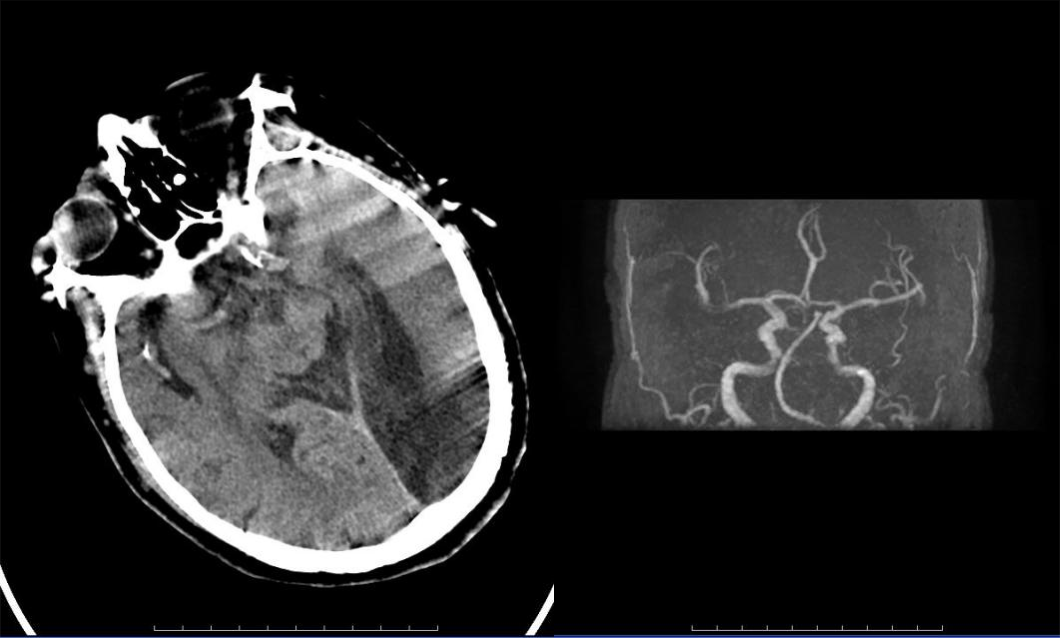

病历三:患者,78岁女性,因左侧肢体无力、右上肢抽搐、言语不清2小时伴意识模糊入院。

介入团队采取上述同样技术取出条块状暗红色血栓,质韧,考虑为心源性栓塞。

大脑中动脉M1段分叉部以远闭塞,大脑中动脉上干开通,取出血栓。